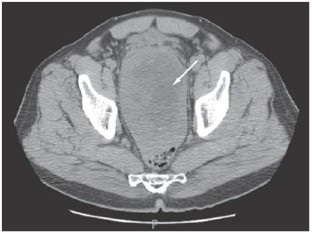

Investigations Upon re-presentation, investigations included measurement of serum PSA levels, pelvic CT, transrectal ultrasoundguided prostate biopsy, histological examination of the biopsy specimen and immunohistochemical staining.